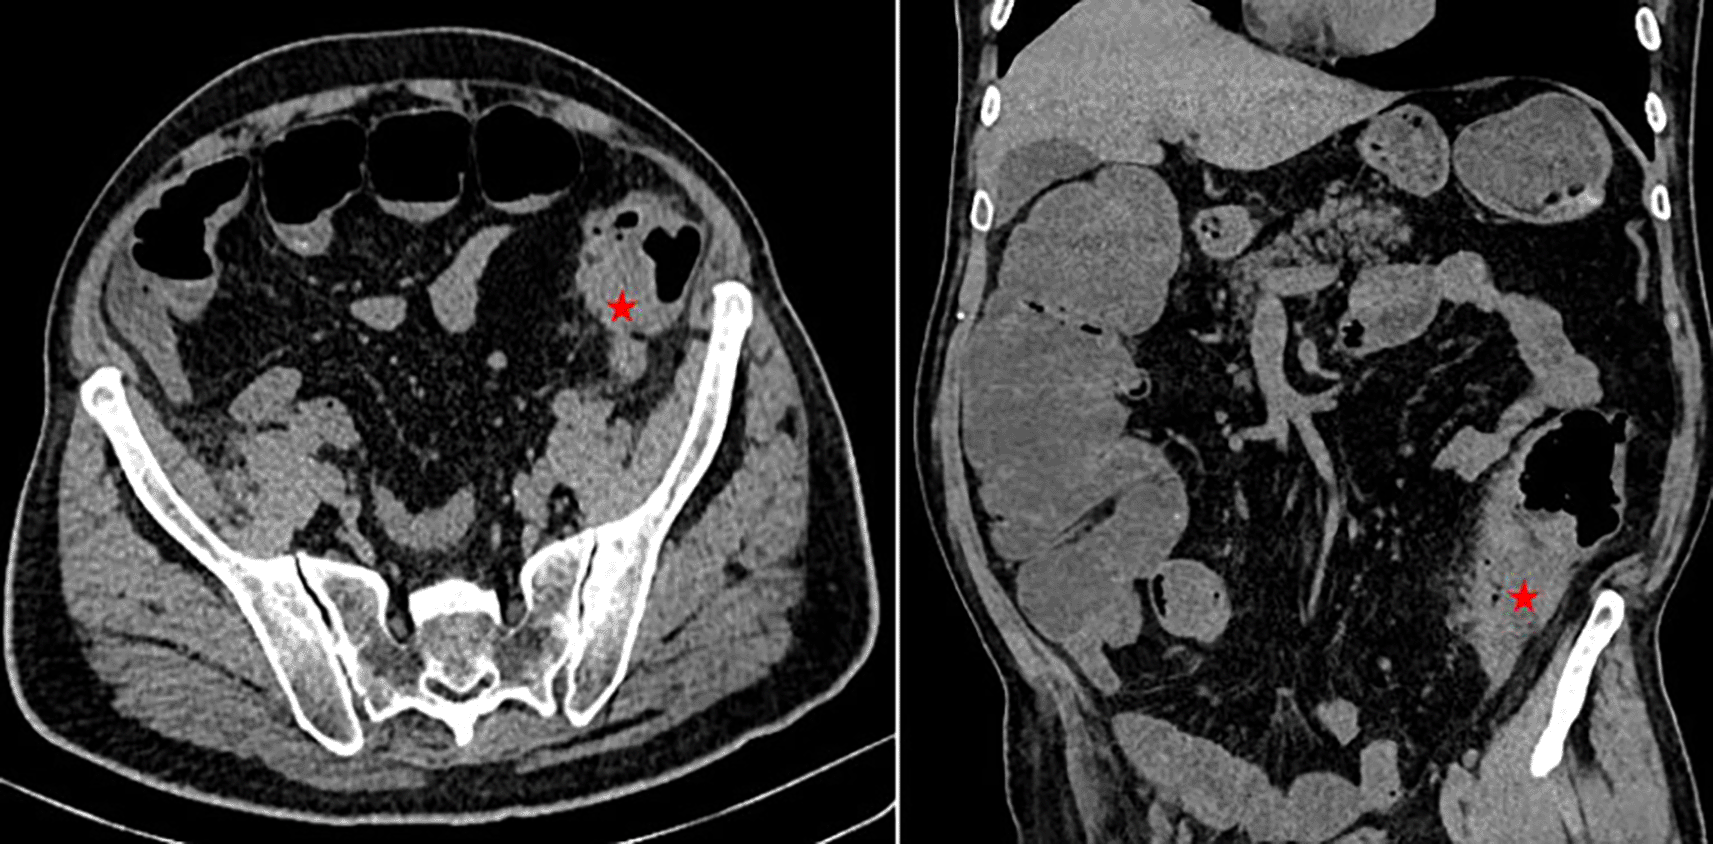

A 68-year-old Tunisian man, with a history of diabetes, hypertension, penicillin allergy, and renal failure, with no prior surgical history, presented to the emergency department with abdominal pain, vomiting, and bowel obstruction. The patient reported a similar symptomatology over the last two months, which resolved spontaneously. He also complained of chronic abdominal discomfort. On examination, he was hemodynamically stable. There was no fever. The abdominal examination revealed a distended and resonant abdomen, tender throughout, with a palpable mass in the left iliac fossa. The laboratory tests were normal, except for a previously known renal failure. We followed up with an abdominal CT scan without contrast, which revealed an acute intestinal obstruction upstream of a suspected obstructive tissue process at the sigmoid colon, with associated satellite lymph nodes and a dilated cecum measuring 12 cm (Figure 1). Emergency surgery was decided after a brief resuscitation. Exploration of the abdomen by midline laparotomy revealed a mass in the sigmoid loop, measuring 7 cm along its major axis, adherent to the omentum, the parietal peritoneum, and the posterior wall, with dilation of the entire upstream colonic frame. The cecum was dilated to 13 cm with a weakened, pre-perforative wall. We underwent a total colectomy with ileostomy and distal end closure (Figure 2). The postoperative recovery was uneventful. Gross pathologic examination of the surgical specimen revealed a stenosing lesion of the sigmoid colon with ulcerated surface mucosa. Histological examination showed acute inflammatory reaction and abscess formations surrounding clumps of short branching basophilic filaments stained with PAS (Periodic Acid Schiff). Dense fibrosis was associated. There was no granulomatous inflammation (Figures 3, 4). Actinomyces infection was confirmed. The patient was then placed on long-term doxycycline and Bactrim. Upon follow-up, he was seen regularly for 9 months. No recurrence has been diagnosed. The restoration of bowel continuity was postponed until completing a full year of antibiotic therapy.